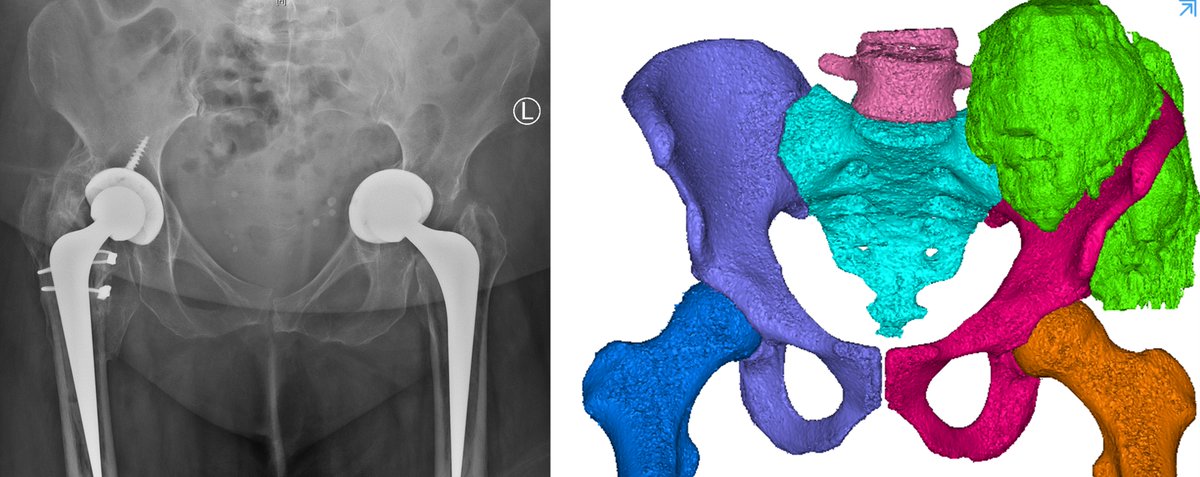

Exciting news! I received the NOA for my NIH application. PCD CT is coming to MD Anderson Cancer Center and Texas Medical Center! Many opportunities like new imaging contrast agents shown from Ryan Roeder (JMI 2019). Thank you NIH and MARS Bioimaging. #radiology #medphys #innovation

.MiNDFOOD caught up with @UCNZScience Professors Phil and Anthony Butler to discuss their revolutionary MARS Bioimaging 3D scanner and their journey from innovation to commercialisation. #UCScience #UCResearch HIT Lab NZ University of Otago bit.ly/3tA09wV

MARS Bioimaging CHUV / Centre hospitalier universitaire vaudois 🏥 Discover #CERNImpact in medical imaging (2/5) 📟 By taking precise pictures without using a contrast agent, MARS Bioimaging scanner, based on CERN technology, promises significant progress in diagnosing and monitoring hand and wrist fractures. #CERNKT ➡️home.cern/news/news/know…

Artificial intelligence (AI) in spectral photon-counting CT image reconstruction. University of Canterbury In this video, UC Senior Lecturer James Atlas shares his experience working with AI and the MARS Imaging System. youtu.be/nTgEyjQhxPU